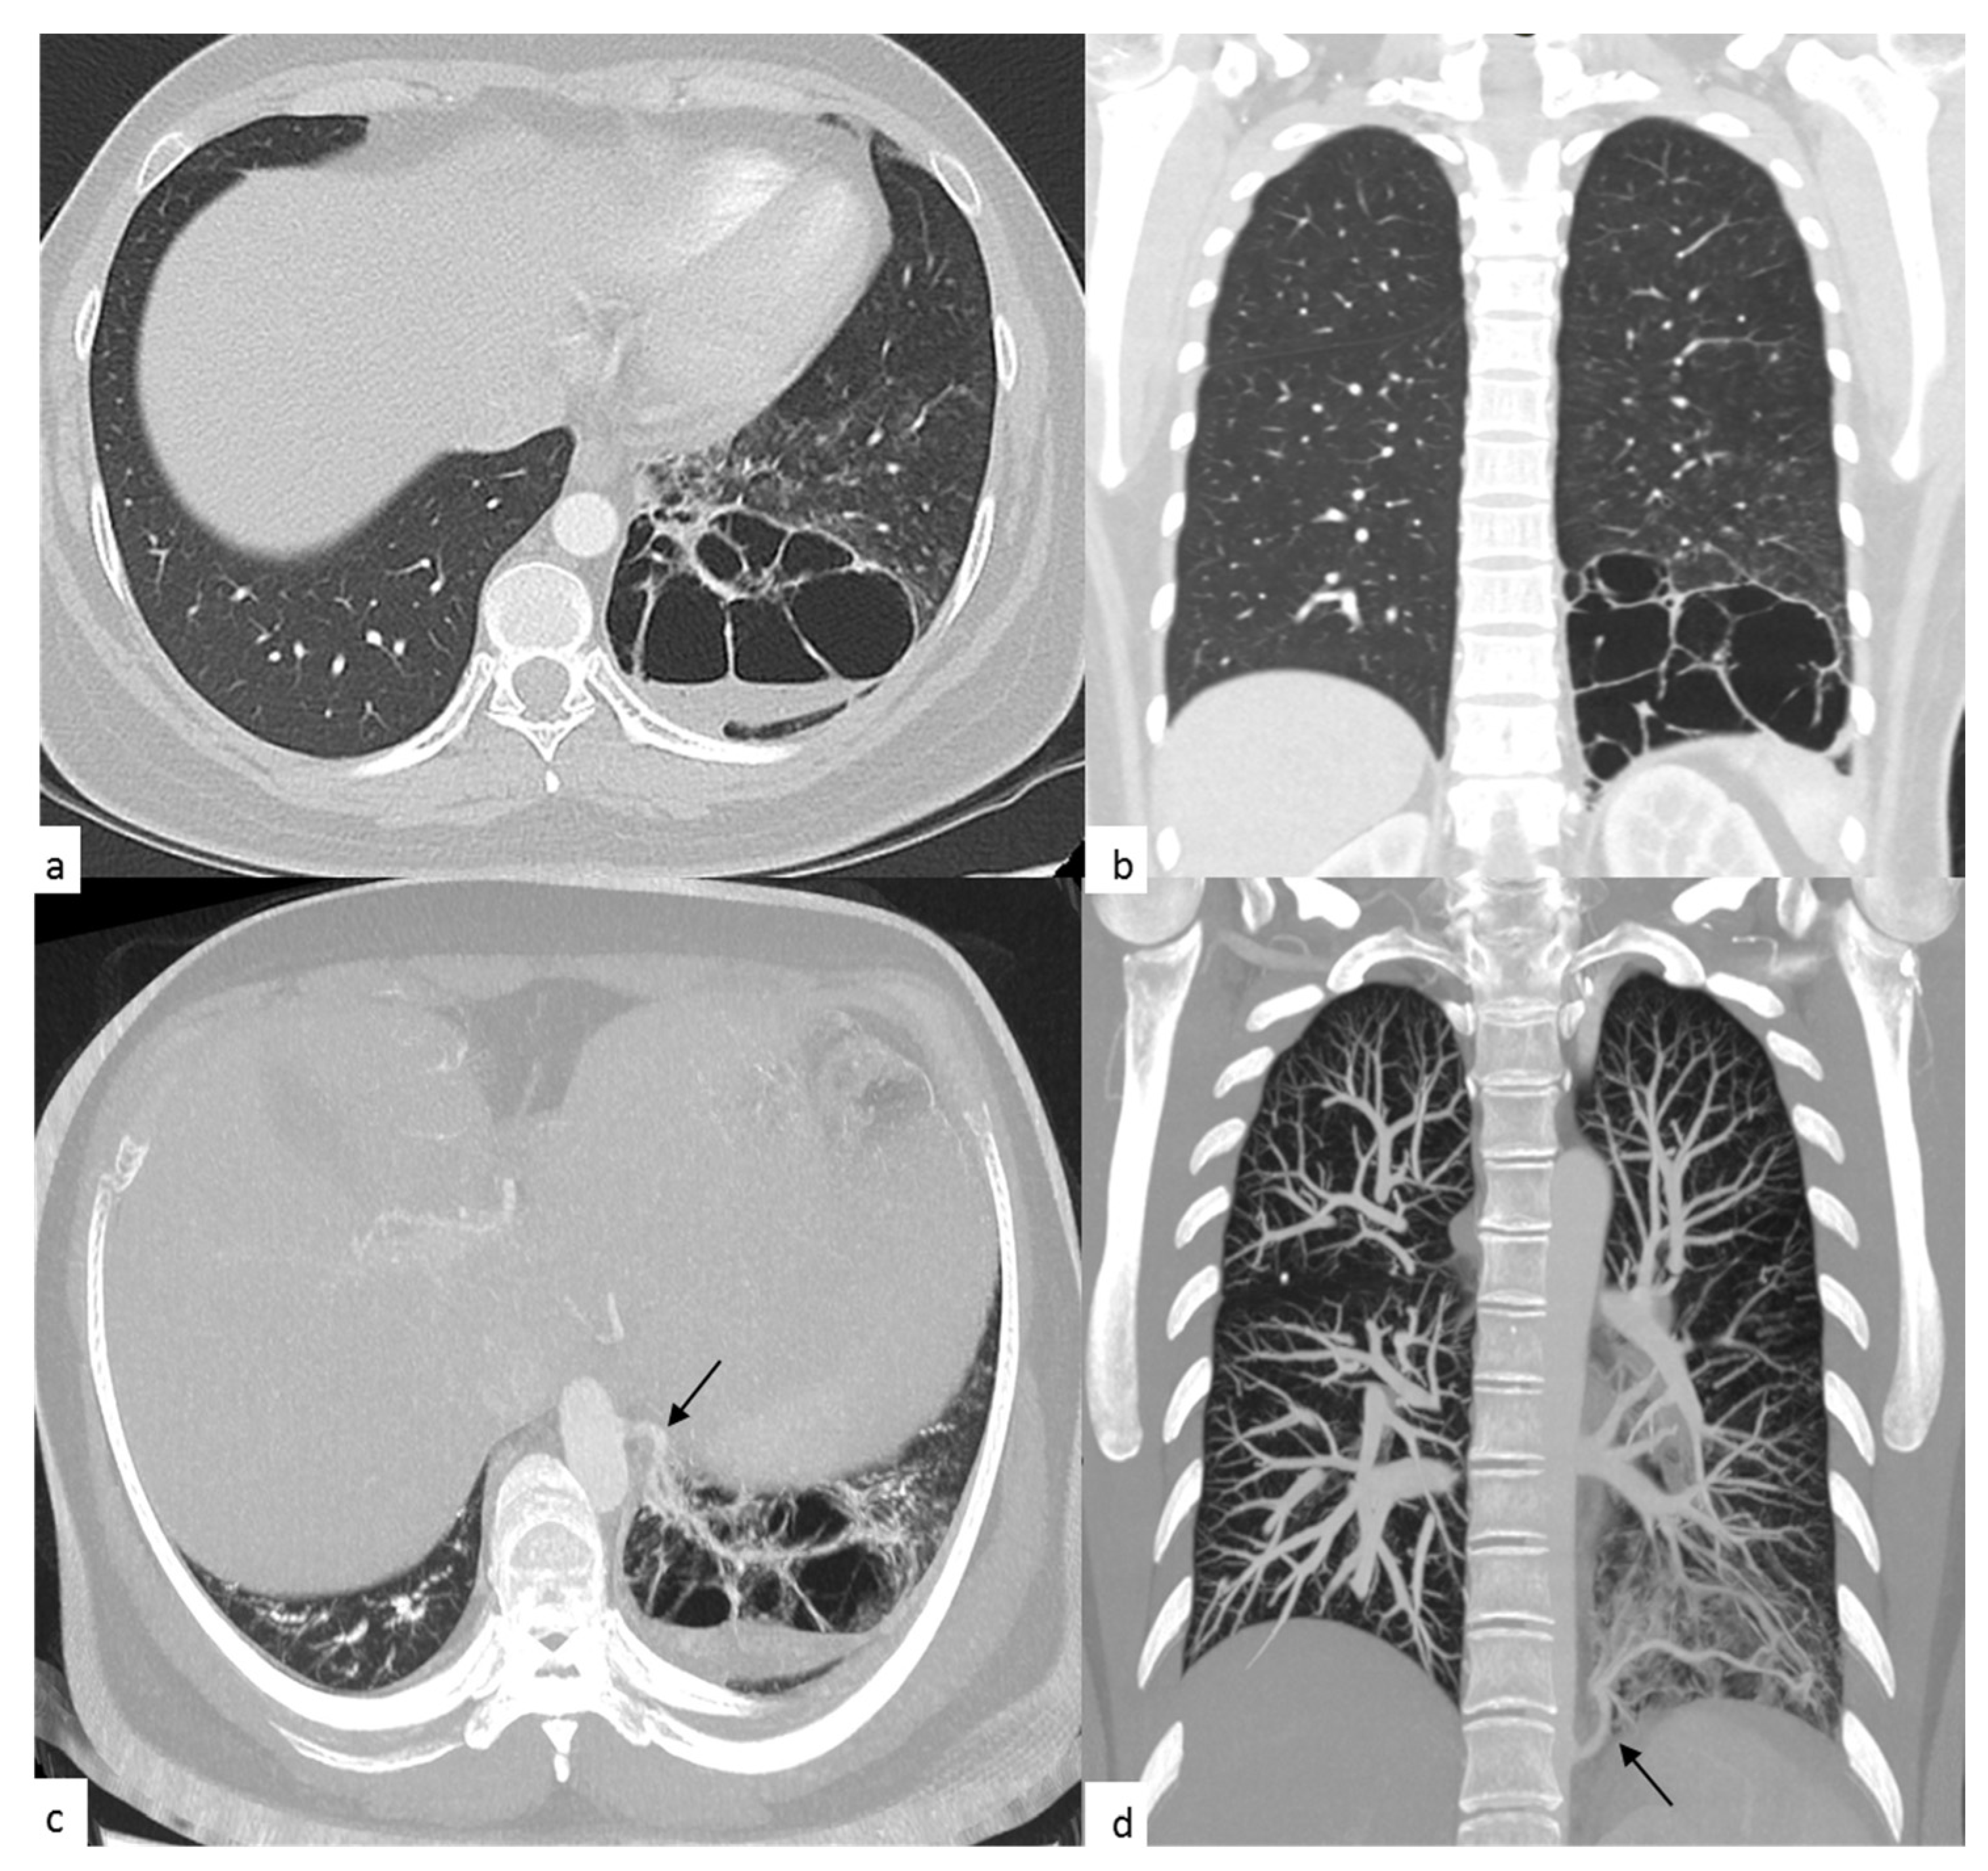

2. Case Presentation